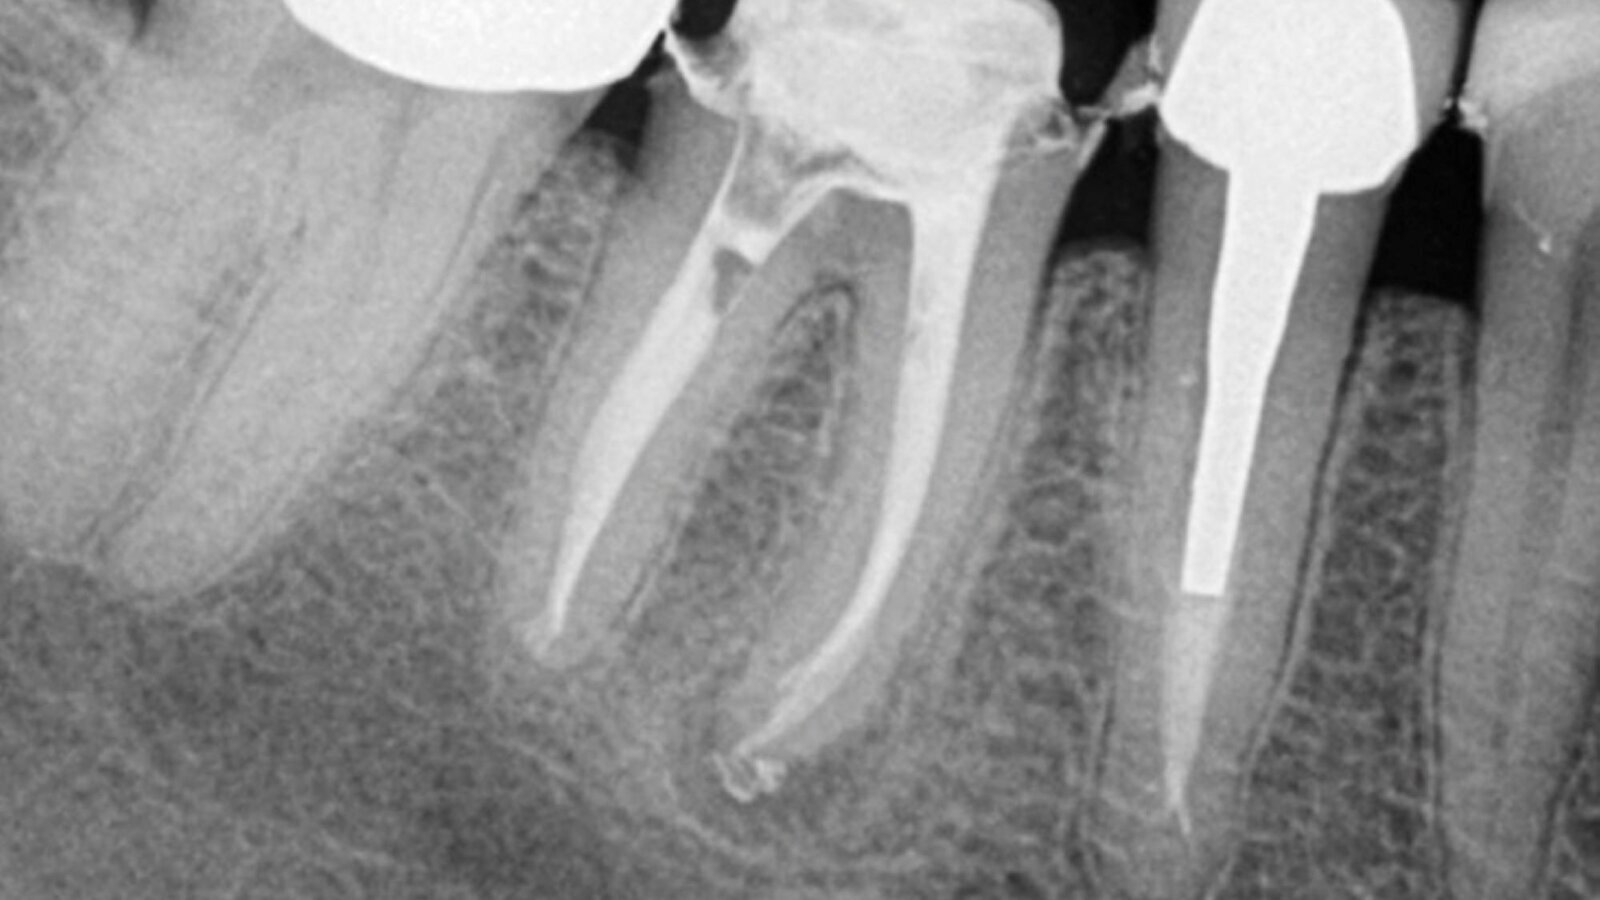

Slučaj 1 – Slika br. 2: Inicijalni periapikalni Rtg snimak

Slučaj 1 – Slika br. 3: Periapikalni kontrolni Rtg snimak nakon godinu dana od tretmana

Pacijent je upućen zbog nelagodnosti u donjim zubima koja je prerasla u pulsirajući bol. Nakon pregleda i rendgenskog snimanja, kod pacijenta je konstatovano da ima problema na prvom donjem molaru i premolaru. Prethodni kanal korena nije bio urađen na nivou standarda i izgleda kao obturacija sa jednim konusom (Slika br. 1). Pacijentu je predočen plan lečenja koji uključuje ponovno lečenje i premolara i molara i na kraju zamena obe krunice. Prošao sam kroz krunice za oba zuba u istoj sesiji. Kao što je ranije opisano, turpije koje sam koristio bile su Traverse 25 08 17 mm, a zatim se Zenflex 35-30-25 06 sužavaju do radne dužine. U ovom slučaju dodao sam konus 35 04 kao turpiju za proširenje na vrhu. Urađena je 3D obturacija pomoću elements IC za oba zuba. 12 meseci nakon tretmana pozvao sam pacijenta na kontrolu (Slika br. 2). Primetio sam da je zarastanje na oba zuba gotovo u potpunosti završeno, sa prelepom obturacijom sistema korenskih kanala i više izlaza. Krunica na molaru je zamenjena, ali na žalost krunica na premolaru nije, na snimku se vidi neka vrsta unutrašnjeg nakupljanja, te sam obavestio pacijenta da to može da ugrozi uspeh lečenja premolara.